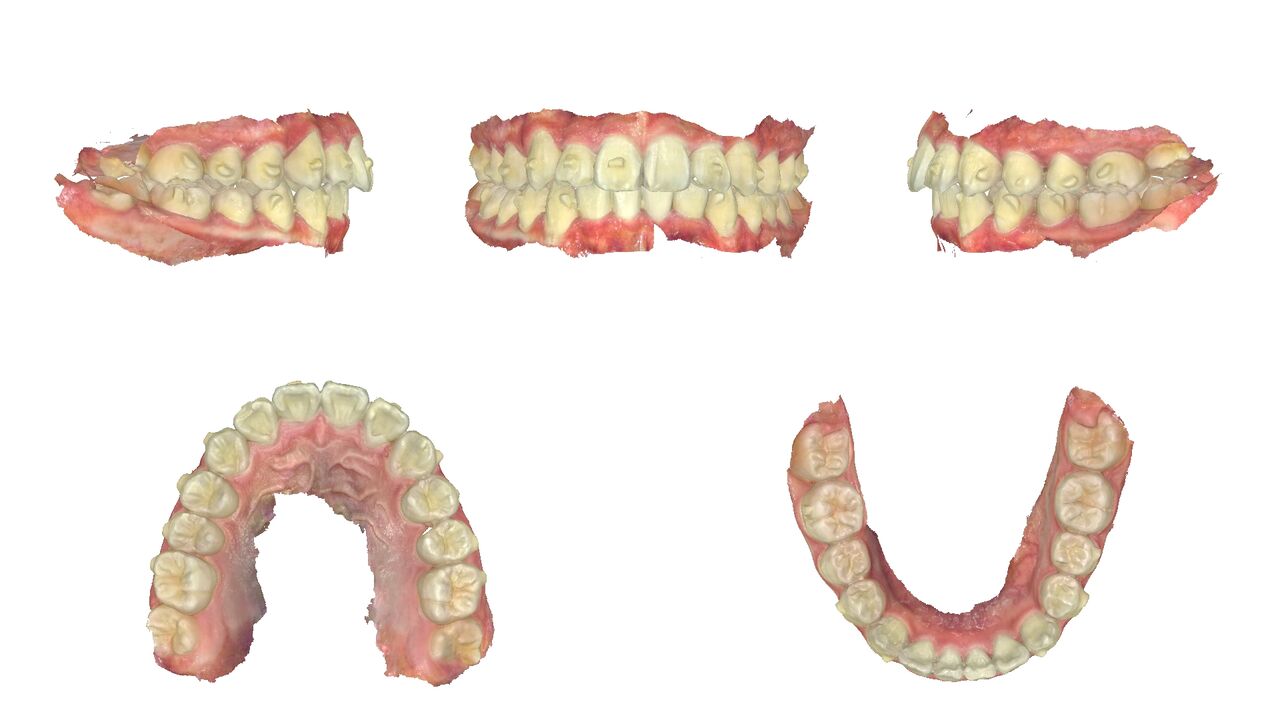

2025年1月5日 わずか9か月後の状態。

上の歯。引っ込んだ歯が歯並びの中に納まっている。

下の歯。こちらも歯並びの中に納まっている。

横からは、やや出っ歯だったのが、出っ歯感はなくなった。